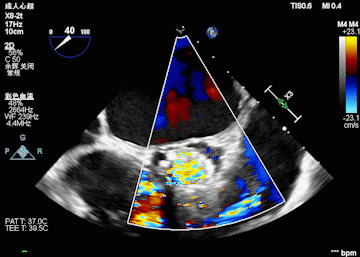

l 术后即刻超声评估

术中情况:术中超声及造影评估,左冠灌注未受影响,瓣膜释放后无明显下滑,洪浪院长术中使用VitaFlow Liberty™进行操作,并精准释放,超声及时辅助评估,VitaFlow二代可回收功能给术者增加信心,可以更放心、大胆的挑战高风险病例。

术中球扩后超声影像

术后超声影像

术后压差对比

在多学科协作下,江西省心血管病医院完成江西省首例VitaFlow Liberty™,进入电动可回收TAVR新时代!该患者主动脉瓣重度狭窄,且CT评估左冠高风险,洪浪院长TAVR团队默契配合,术前充分评估每个重要环节及其应对措施,为手术的成功奠定了基础。患者平均跨瓣压差由术前的67mmHg降至1mmHg,少量瓣周漏,手术取得圆满成功。相比传统开放手术,经股动脉的TAVR不需要体外循环,不需要开胸,没有明显失血,麻醉时间更短,创伤小、恢复快。主动脉瓣膜介入治疗从10年前的前沿探索到现在逐步成为一种主流手术模式,我国瓣膜介入技术正在发生翻天覆地的变化,在此背景下,江西省心血管病医院洪浪院长带领团队不断创新,不断提高团队技术水平,挽救患者生命和提高老年患者生活质量。